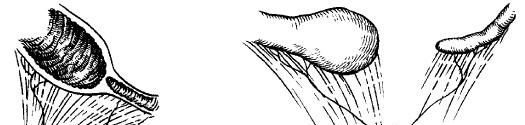

Bağırsaq borusunun inkişaf qüsurları arasında stenozlar və atreziyalar üstünlük təşkil edir, tək və ya çoxsaylı olurlar. Bu qüsurlar hər 5000 canlı yenidoğulmuşun 1-də rast gəlir və onların 95-96%-i OBB və acı bağırsaq səviyyəsində yerləşir (şək. ).

Şək 1. Onikibarmaq bağırsağın atreziyası variantları (sxematik təsvirlər)

Atreziyanın tipləri:

- I tip (23%) – bağırsağın mənfəzində membran olur, bağırsağın uzunluğu normaldır, müsariqə defektsizdir, bağırsağın fasiləliyi pozulmur. Membranın defekti (dəliyi, dəlikləri, yarığı) olduqda bağırsaq keçiriciliyi az pozulur və ya pozulmur, tam membran olduqda isə pozulur.

- II tip (10%) genişlənmiş proksimal seqment kor qurtarır və müsariqənin kənarından keçən qaytanla bağırsağın növbəti, yaprıxmış seqmentinə birləşir. Bəzən belə seqmentlər bir neçə olur və onları bir-biri ilə qaytanlar birləşdirir. Qaytanların mənfəzi olmur. Müsariqə defektsizdir, bağırsağın uzunluğu normal hədlərdə olur.

- IIIa tipi (16%) II tip kimidir, lakin müsariqənin V-şəkilli defekti olur və bağırsaq kiçilir.

- IIIb tipi və ya “qabıqsız alma dilimi” – “apple peel” (19%) acı bağırsağın proksimal hissəsinin atreziyası (çox vaxt malrotasiya ilə), böyük hissədə yuxarı müsariqə arteriyası və ya onun şaxələri olmur, müsariqənin böyük deffekti müəyyən edilir.

- IV tip (20%) atreziyada bağırsaq ilgəkləri sosisşəkilli görkəm alır, və ya I-III tip atreziyaların kombinasiyası müəyyən edilir. Bağırsaq xeyli qısalır (şək 2. ).